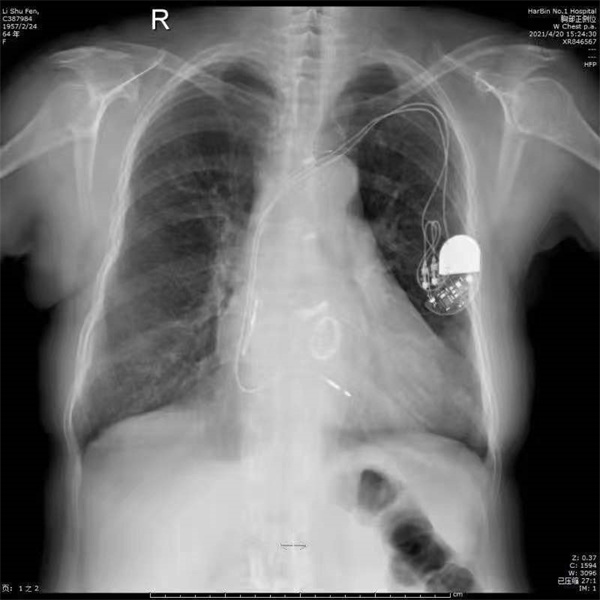

2008 年,李女士又因「病態竇房結綜合徵」再次去趙侃科室就診,給予「心臟永久性生理性雙腔起搏器」治療,患者心律(心率)恢復正常。

2021年4月,李女士因「陣發性胸痛,胸悶、心悸30年余,加重一周」到趙侃的科室入院治療。查體:血壓140/100mmHg,心界輕大,心率86次/分,心律絕對不規則,二尖瓣、主動脈瓣區聞及機械瓣音,瓣膜啟閉音等良好。輔助檢查心電圖顯示:心房纖顫,心率:86次/分伴ST-T變化;心臟超聲顯示:1、左心增大,余房,室內徑正常範圍,右心內可見起搏器電極強回聲;2、室間隔增厚,左室壁厚度正常範圍,左室壁運動幅度及收縮期增厚率普遍減低,下壁明顯減低;3、主動脈瓣及二尖瓣可見機械瓣強回聲,瓣架及結構固定,瓣周圍未見明顯異常回聲,未見明顯瓣周漏,瓣葉活動良好,余瓣膜結構未見異常,CDF:收縮期三尖瓣少量反流信號,舒張期主動脈瓣可見少量返流信號;4、主、肺動脈內徑正常範圍、估測PASP:49mmHg; 5、房、室間隔連續完整;6、三維超聲心動圖:各房室腔內璧較光滑、房室瓣及半月瓣顯示清漸、TV舒張期二尖瓣環運動速度減低,EF:55%。凝血測定:PT 國際標準化比值 INR 1.49;Y-GT 104.0lU/L;FT3 2.49pg/ml、FT4 1.15ng/dl,TSH 5.3uIU/ml、 血清促甲狀腺激素 5.750ulU/ml; 糖類抗原CA724 26.30U/ml.細胞角蛋白19片段4.65ng/ml。確定診斷為:不穩定型心絞痛、 冠狀動脈粥樣硬化性心臟病;心律失常、 心房顫動;風濕性二尖瓣、主動脈瓣三尖瓣聯合瓣膜病; 二尖瓣機械瓣置換狀態、主動脈瓣機械瓣置換狀態 、三尖瓣成形術後;心臟永久性生理性雙腔起搏器術後;高血壓、高心病;亞臨床甲狀腺功能減退。